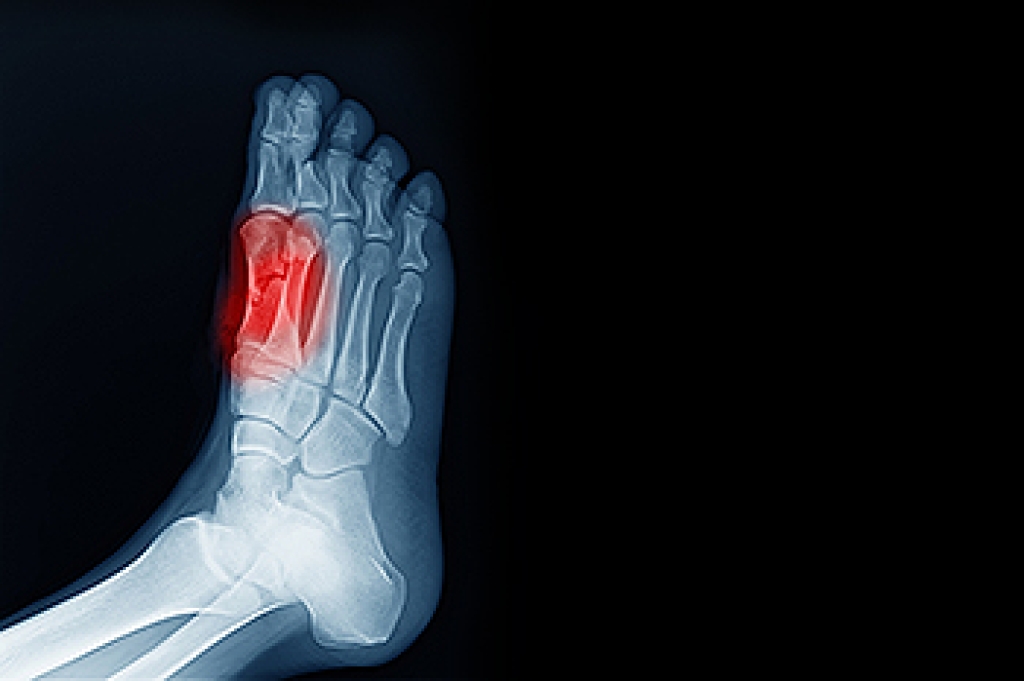

How Do Blisters Form?

Blisters on the feet are often the result of constant friction of skin and material, usually by shoe rubbing. Walking in sandals, boots, or shoes that don’t fit properly for long periods of time can result in a blister. Having consistent foot moisture and humidity can easily lead to blister formation.

Prevention & Treatment

It is important to properly care for the affected area in order to prevent infection and ease the pain. Do not lance the blister and use a Band-Aid to provide pain relief. Also, be sure to keep your feet dry and wear proper fitting shoes. If you see blood or pus in a blister, seek assistance from a podiatrist.